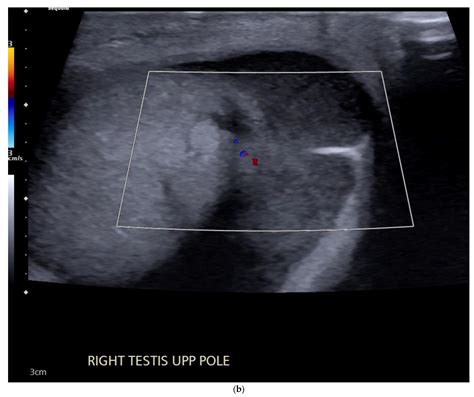

Interpreting the results of a testicular ultrasound requires expertise and experience. Healthcare professionals look for specific characteristics that may indicate the presence of testicular carcinoma. Some of the key features that can be identified on ultrasound include:

• Size and Shape: Testicular carcinoma often appears as a solid mass with irregular borders. The size and shape of the mass can provide clues about its nature.

• Echogenicity: The echogenicity of the mass refers to how it reflects sound waves. Testicular carcinoma typically appears hypoechoic, meaning it reflects fewer sound waves than the surrounding tissue.

• Vascularity: The blood flow to the mass can be assessed using Doppler ultrasound. Increased vascularity is often associated with malignant tumors.

• Location: The location of the mass within the testicle can also provide important information. Testicular carcinoma often arises from the seminiferous tubules and can be found in various parts of the testicle.